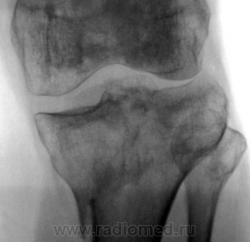

Консолидированый перелом проксимального эпифиза большеберцовой кости с повреждением наружного мениска и крестообразных связок ( вернее после их пластического восстановления ).

Александр Викторович,стояние отломков можно считать удовлетворительным?.+ вторичный ДОА+"пятнистый" остеопороз с участками остеосклероза.

стояние отломков, по истечении года, большого значения уже не имеет, главное что консолидация наступила, связочный аппарат восстановлен, в данном случаи нужно оценивать функцию, опорность, объем движений в данном суставе. Хотя внутренний мыщелок б\б кости просел прилично...